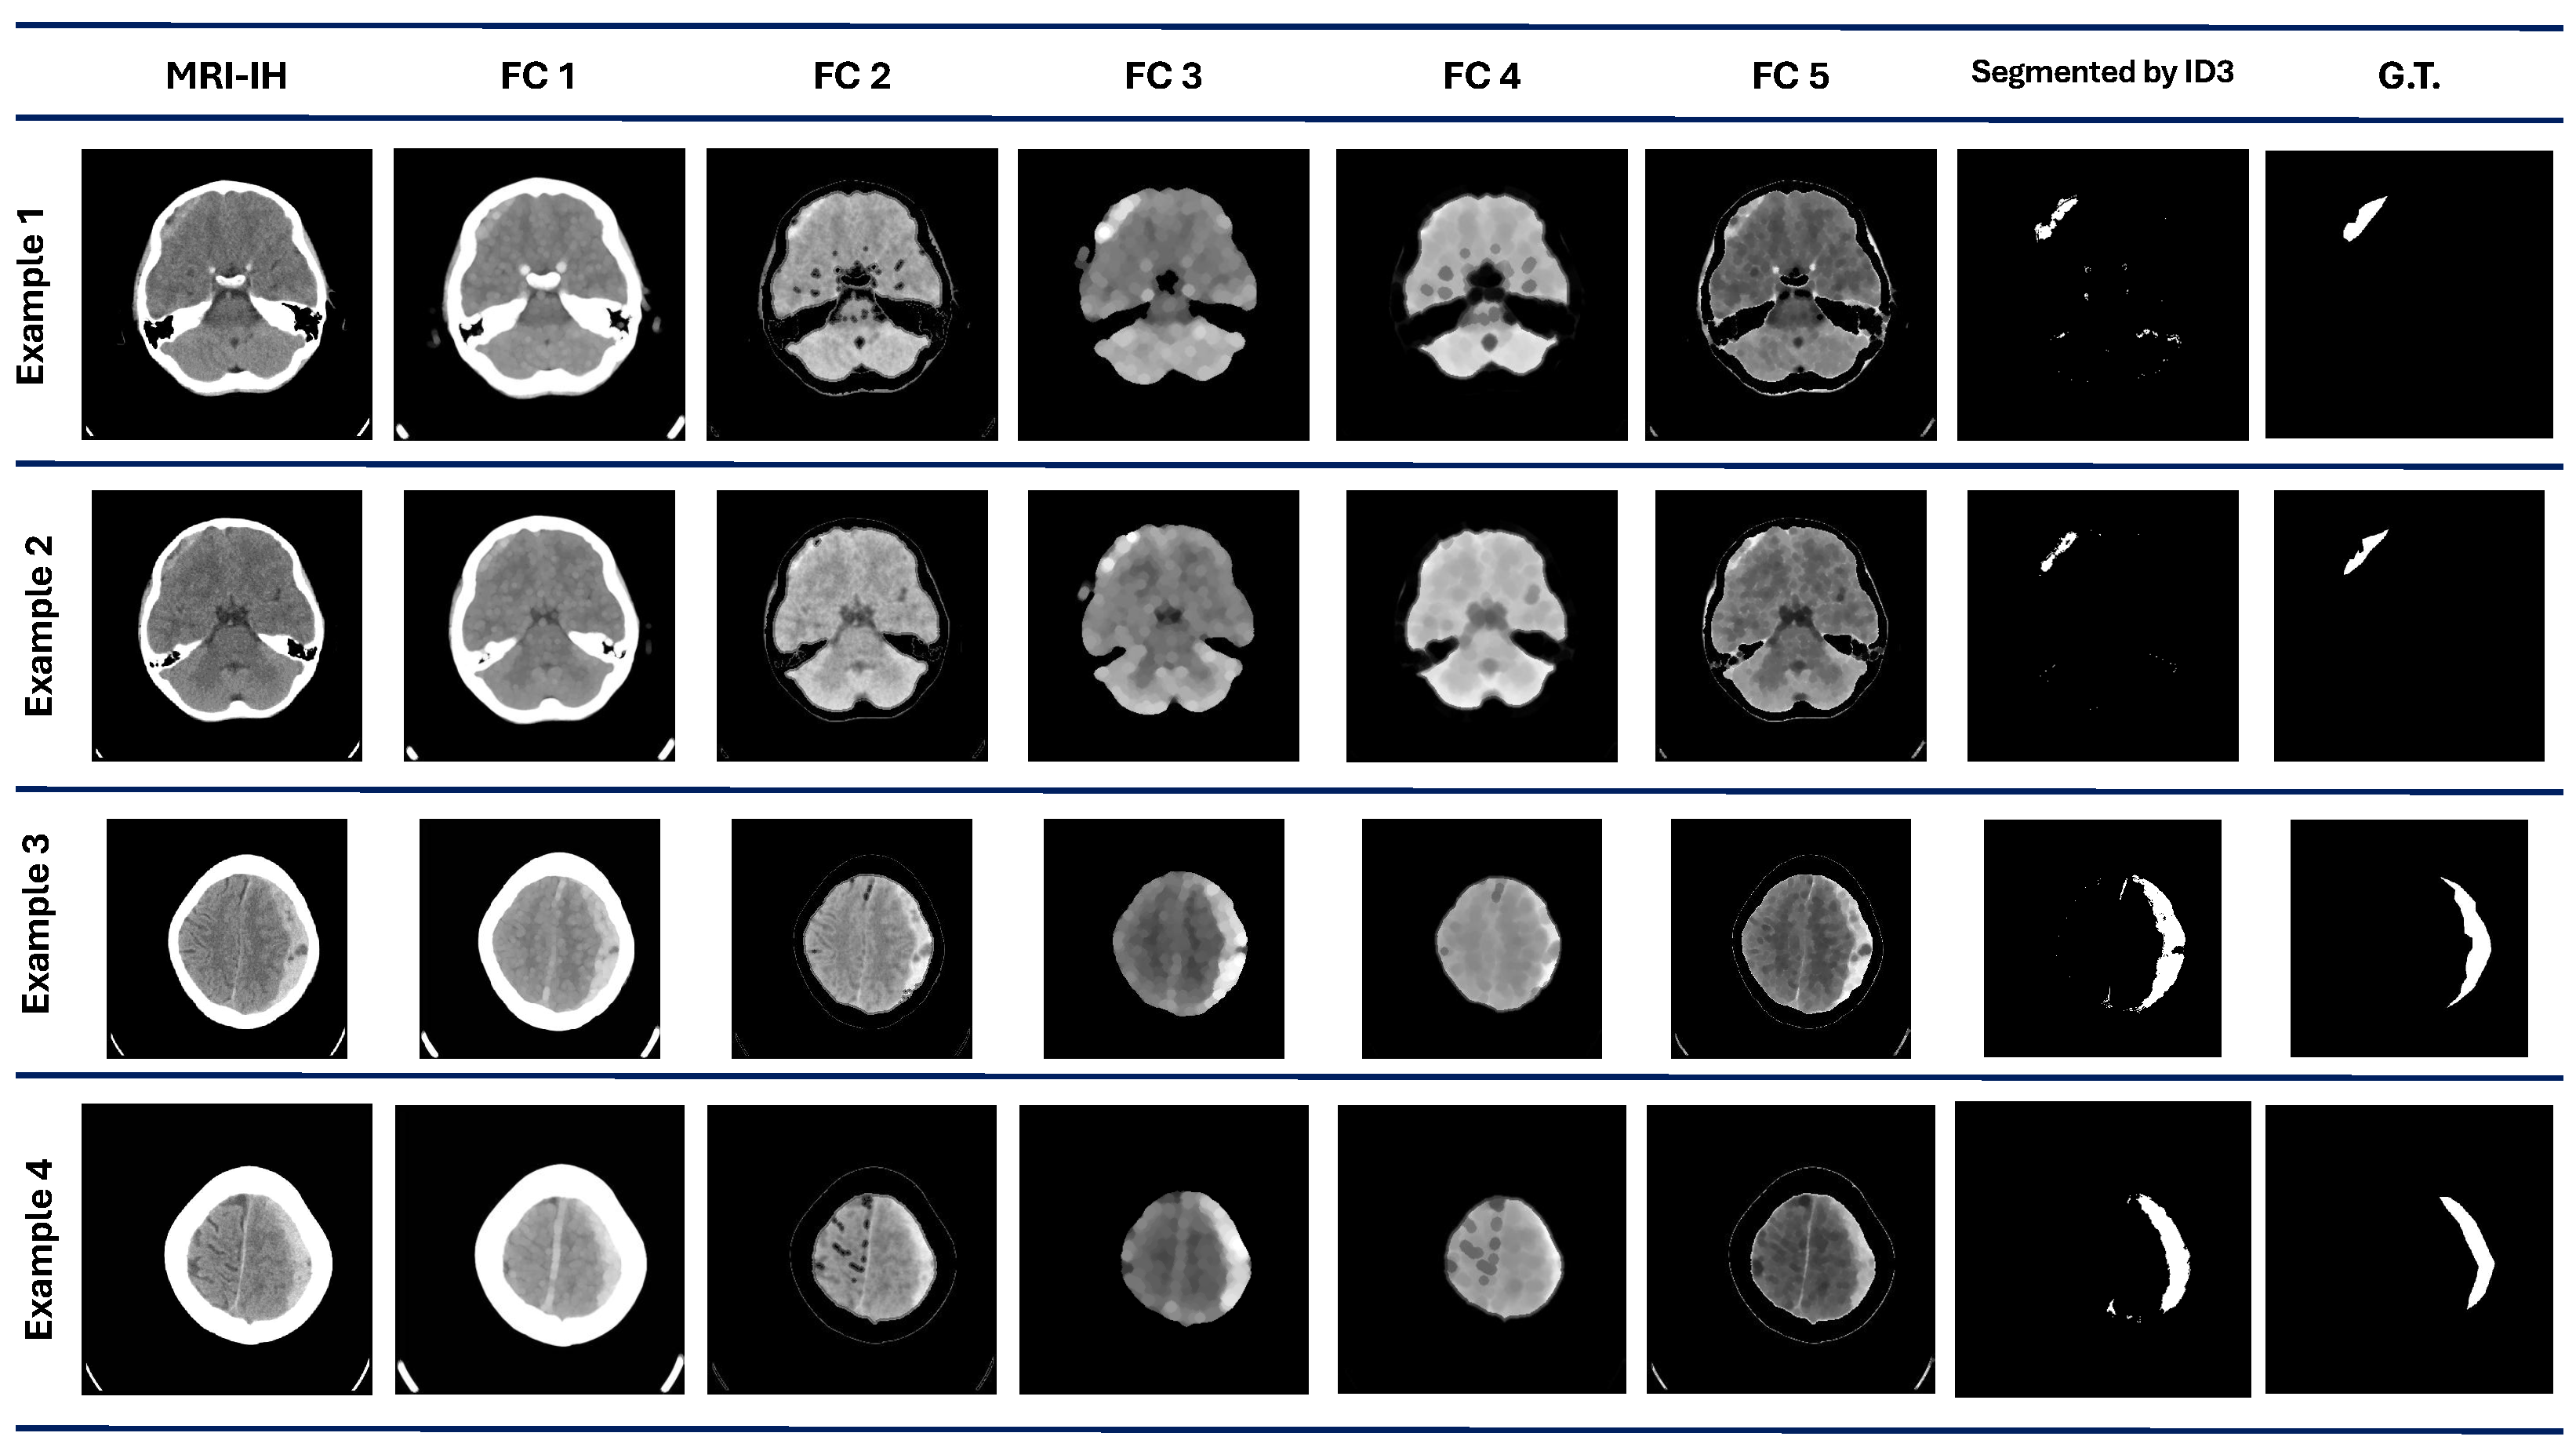

Finally, in the MRI-IH, the algorithm performance achieves a mean and median value of 0.44 and 0.43, respectively. This dataset was the most challenging part of the proposal. The best value achieved is the lowest compared to the other datasets, with only a 0.56 DICE value. Also, it has the second-lowest value for the worst performance in the different datasets. The visual results with this dataset are shown in Figure 5. In example 1, the segmentation results show some regions marked as ROI, according to the G.T. Examples 3 and 4 show a good visual performance. However, some regions are discarded and include areas that do not correspond to the ROI.

Figure 5.

MRI-IH dataset results. The first column contains the original images. are the images processed by each best individual for each evolved population. The ID3 column contains the images segmented by the model at the pixel level. The G.T. column contains objective images.

The significant variability is present in the DRIVE dataset, where some outliers exist and correspond to the worst and lowest values. As we can observe in Figure 3, the MRI-IH dataset reflects the difficulty for our method to perform the segmentation, where the ROIs are small regions that are hard to segment.